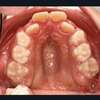

- hypo développement du maxillaire supérieur, étroitesse du palais

On observe une mastication faible et des encombrements dentaires importants.